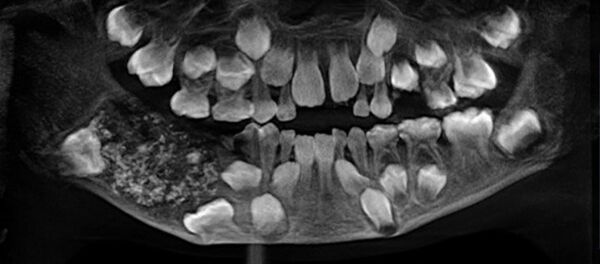

レントゲンを撮り、半円形の物質が入れ歯であることが判明した。男性は緊急入院し、医師らが入れ歯を取り出した。

X-ray shows dentures left lodged in patient’s throat for 8 days - this must have been painful! https://t.co/APnUAbVIXG